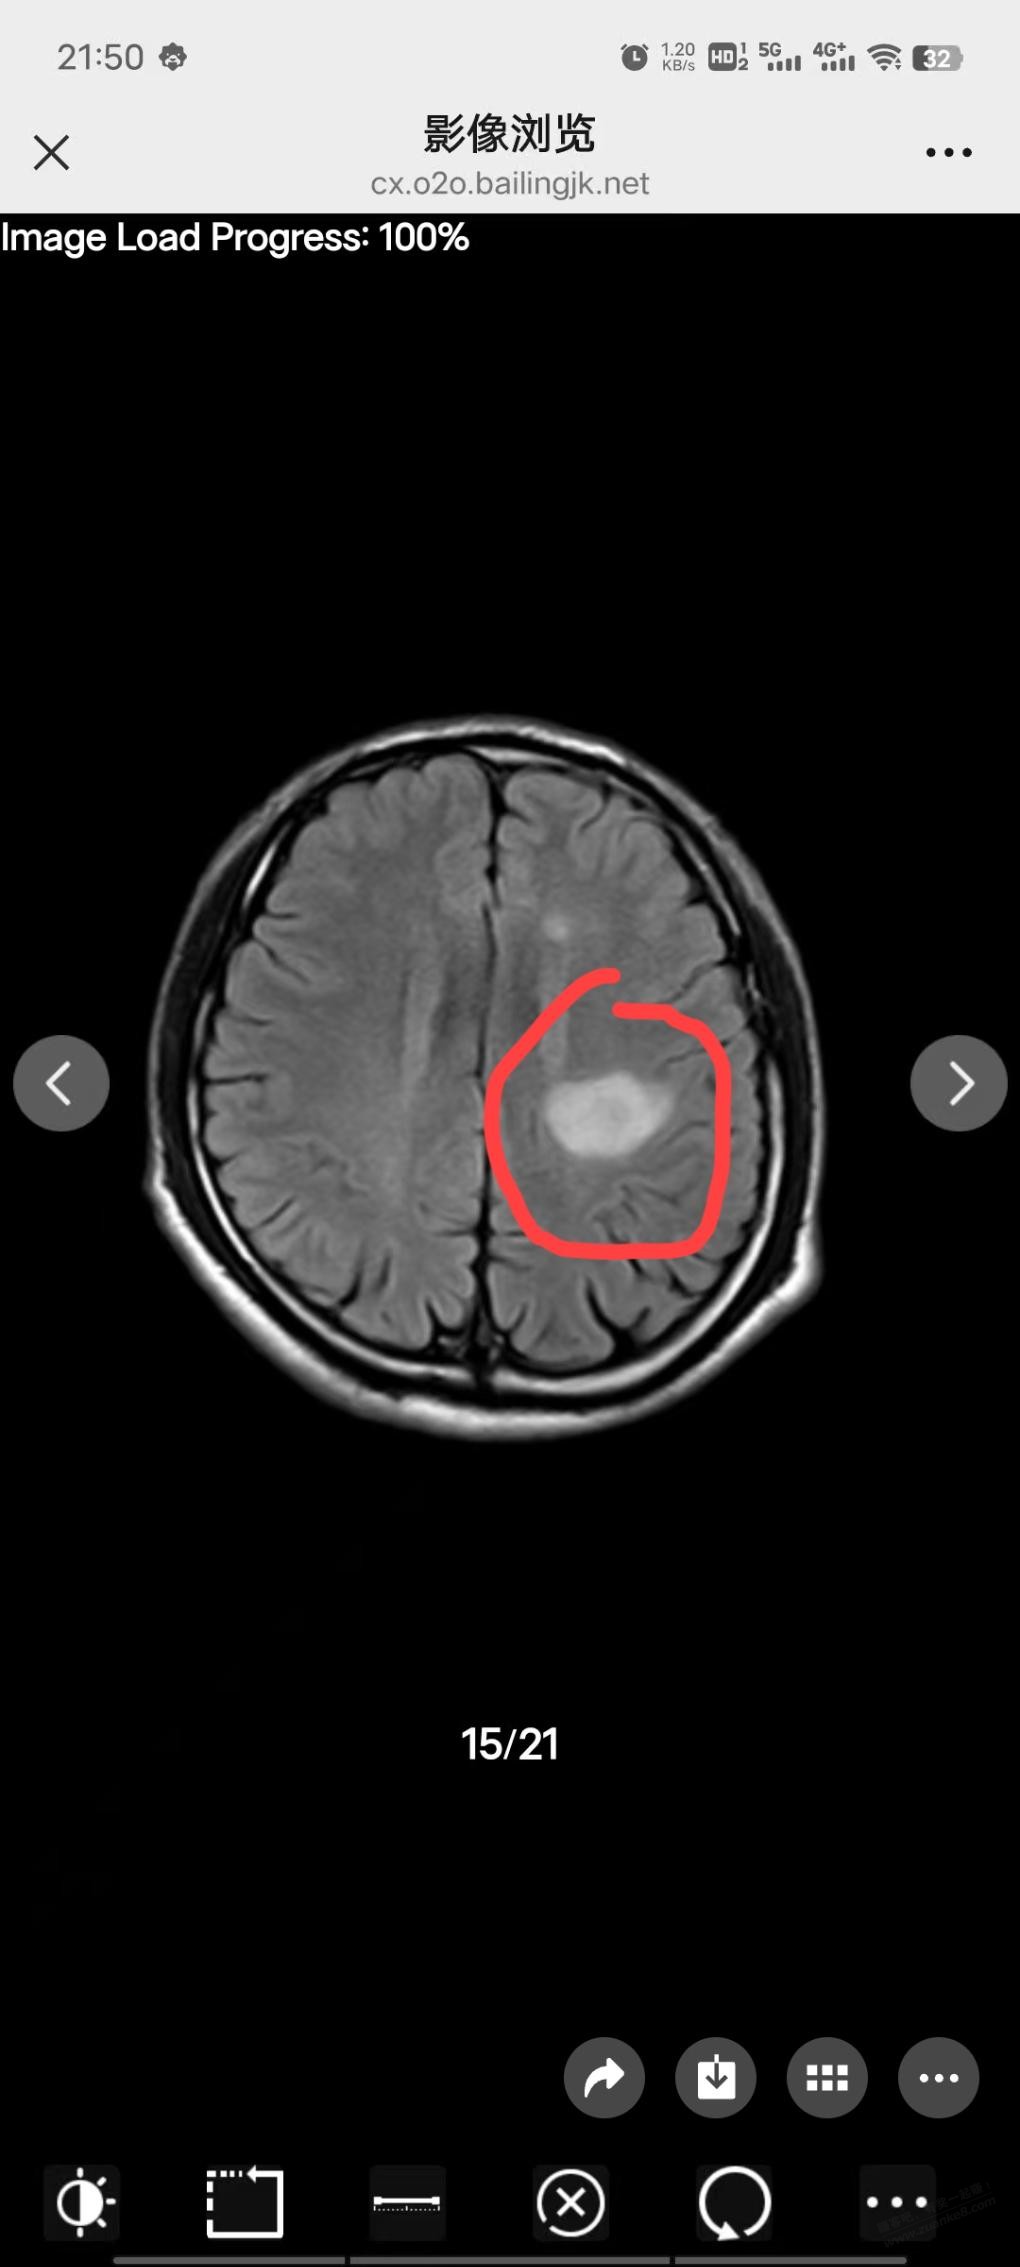

希望是虚惊一场,祝早日康复。看核磁的话大多数神经科医生都会首先怀疑是出血性还是缺血性,如果怀疑脱髓鞘可能还要做肌电图

这种就算不是瘤也肯定是梗,都很惨了,哎,人类在疾病面前还是太难了。。。

妈呀 好大一个阴影啊  人类好脆弱